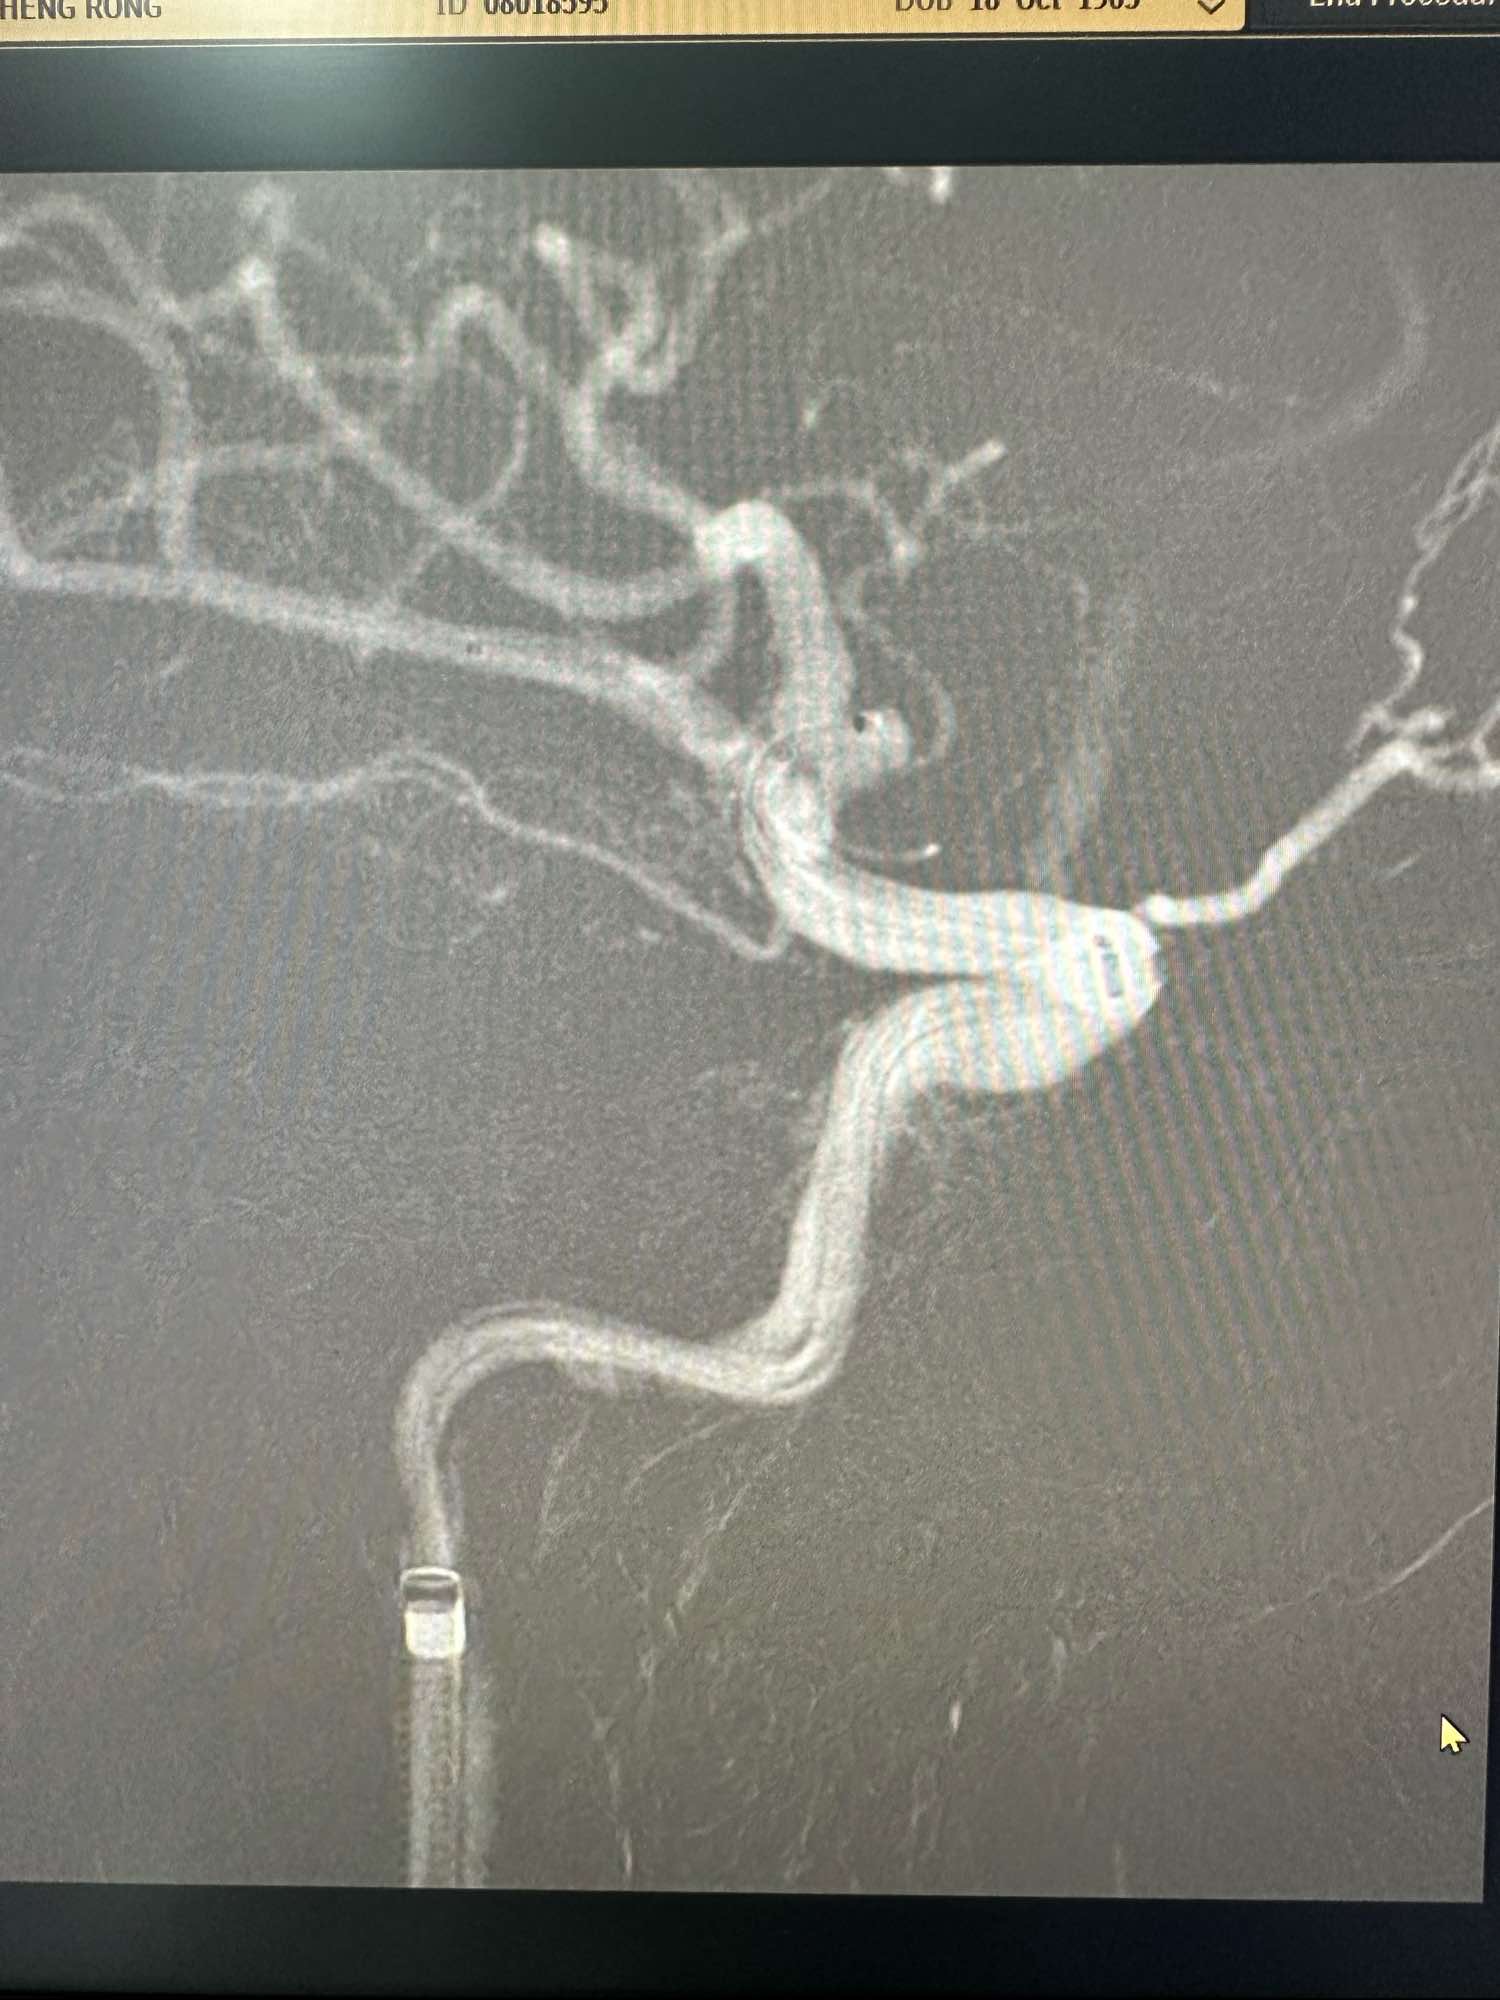

左侧颈内动脉造影正位

侧位

通路为COOK长鞘加上6F的115的银蛇中间导管,刚开始的时候就发现C1痉挛严重.术中给予尼莫通动脉内滴注,痉挛缓解

支架导管选择SL-10,超选下干,角度有点刁钻,采用将支架导管塑形成猪尾巴形态,瘤内成攀后进下干.

Enchon-10弹簧圈导管塑形后直接进入动脉瘤内

第一枚圈选择3*8的加奇的3D,出了几个襻后直接释放Atlas支架3*21

第一枚圈填塞后的形态,圈没有影响上干血流

第一枚圈的形态

后续再次填入2*4的加奇圈,另外一个角度造影见动脉瘤已经不显影

圈的形态

术中发现有血栓,动脉内直接给予新维林8ML,并静脉内持续泵入4ML再次造影见血栓已经完全消失

侧位,术后患者完全清醒,未见特殊异常